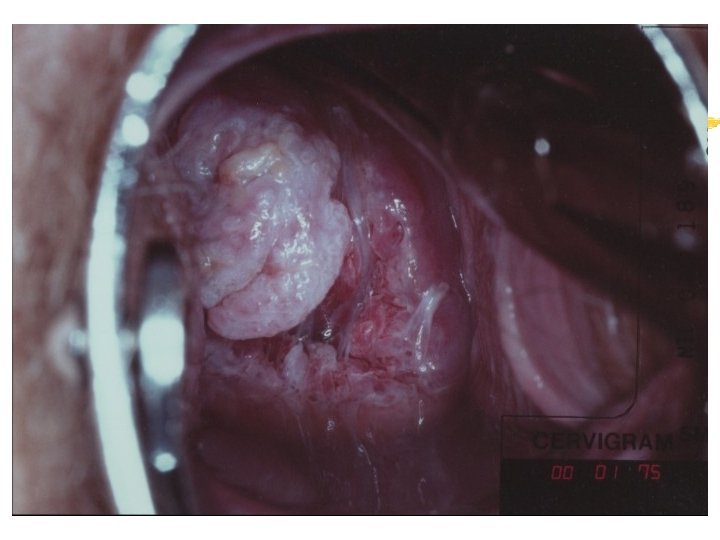

Carcinoma Cervix:

Warning signs of early cervical cancer 1. Yellowish and friable epithelium 2. Abnormal contour 3. Ulceration 4. Atypical vessels 5. Very severe colposcopic atypia 6. Large, significant lesion 7. Canal lesion, going out of range 8. Perimenopausal and post radiation

Mimics of cervical cancer 1. Severe cervicitis e. g. , herpes, syphilis 2. Benign ulceration e. g. , trauma 3. Foreign body reaction 4. Granulomatous cervical conditions 5. Granuloma inguinale 6. Lymphogranuloma venereum 7. Schistosomiasis 8. Cervical condylomata Cololposcopy aids differentiation. Histology is the gold standard